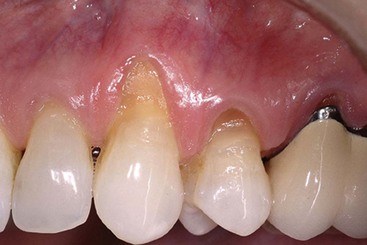

image

Supplement A Figure 63-6 Postoperative view after 1 month.